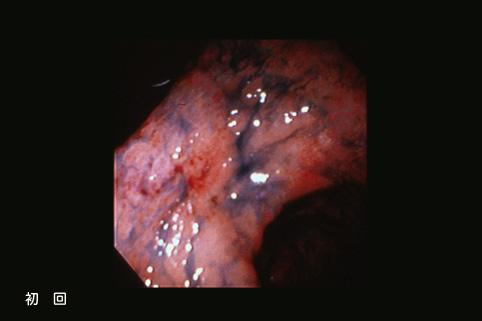

clasificación del pacienteTumor Epitelial Maligno/Adenocarcinoma

parte(separada por órganos)estómago(región)/antro

método de exámenEndoscopia

clasificación ectoscópica de tumoresTipo 0(tipo superficial)/Tipo IIc(IIc+IIb)

diámetro mayor del tumor35 - 40

grado de penetraciónm